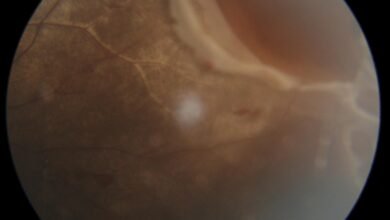

إنقاذ بصر صبي يبلغ من العمر 13 عاماً بعد إصابة نادرة في عينه بسبب كرة الكريكيت تم علاجه في مستشفى أستر منخول

نبض الحدث ــ أحمد بن عبدالقادر يشكل الأطفال حوالي 18.9% من مجمل حالات إصابات العين1، وتمثل حالات انفصال الشبكية في…